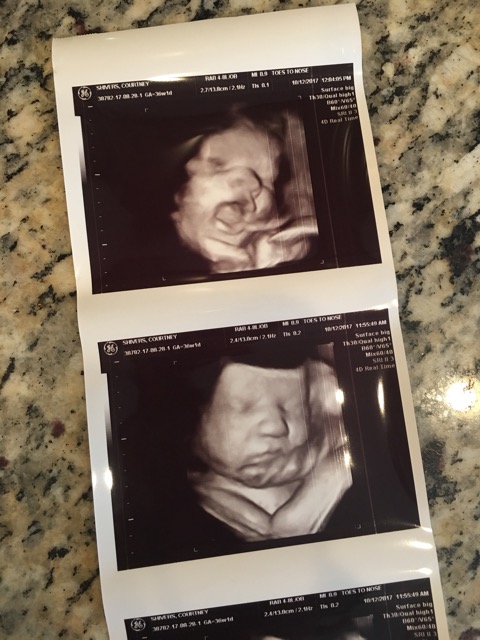

La ecografía 3D “humaniza” aún más al feto a los ojos de los padres y ecografistas. Quizás esto ayude a clarificar los derechos del feto/niño por nacer, y también puede ayudar con las consideraciones éticas. El 3D permitirá una mejor comprensión del comportamiento fetal. Por el momento, nuestro enfoque en el bienestar fetal (“felicidad”) se limita en gran medida al perfil biofísico del tercer trimestre y al Doppler. Con la ecografía 4D podemos ver al feto “feliz” de 12 semanas, no solo saltando, sino también bailando breakdance, kickboxing, saludando y explorando su mundo. Se puede ver al feliz feto del segundo trimestre haciendo expresiones faciales, hurgando la lengua, explorando su cuerpo con las manos e incluso haciendo el signo de la paz hippy u otras señales manuales “gangsta” (Fig. 6). La reacción de los padres y ecografistas al ver esto es especial.

Cara de imagen de superficie 3D en el escaneo anatómico que muestra expresiones faciales y manuales descriptivas.

Nena con actitud.